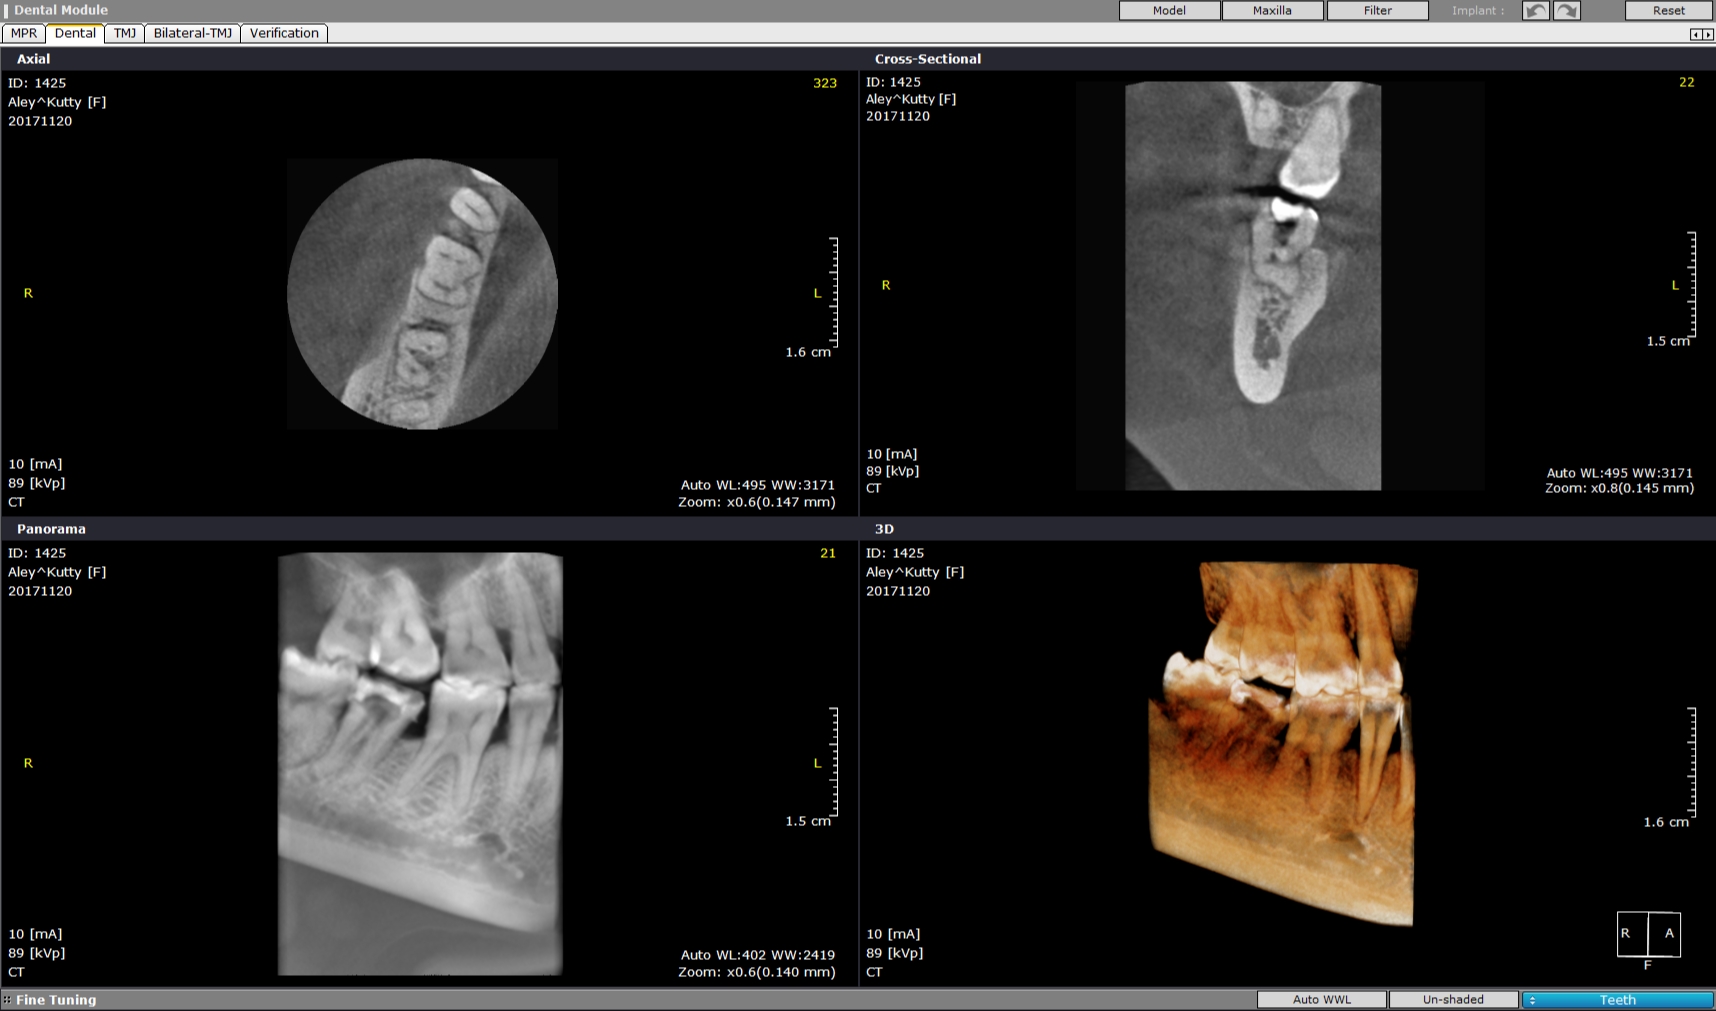

Pt 50 YOF presented with dislodged crown and severe pain in the recently RCT done #31. Started Re-treatment, after cleaning the chamber saw three orifices and finished the canals preparation, but was not sure of the distolinugal. I did not diagnose perforation as there was no bleeding nor patient complained of any pain during the preparation. Later Scan confirmed perforation and was sealed with fiber reinforced composite.